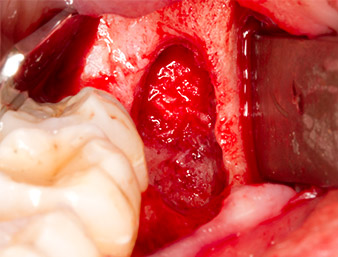

The tissue above the root remnant was not completely ossified and consisted for the most part of granulation tissue modified by inflammation (Fig. 4).

Periapical inflamed tissue was also removed very carefully with a manual excavator. Fig. 12 shows the empty alveole with exposed inferior alveolar nerve.